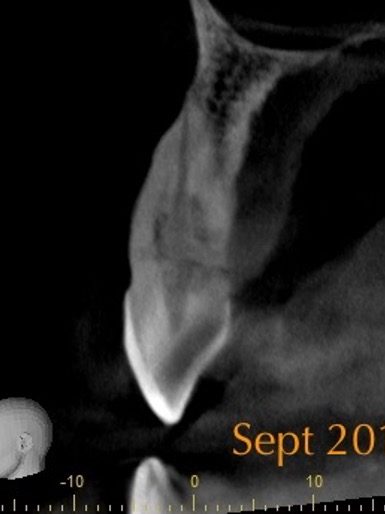

In my opinion CBCT is essential to assess external cervical resorption lesions prior to treatment.

I carried out a clinical study (Patel et al, 2016), which showed periapical radiographs significantly underestimated the size of lesions. They also provide limited information about the location and circumferential spread.

This results in differences in the treatment plan chosen by clinicians on how to best manage the resorption.

Parallax radiographs were also shown to provide no additional benefit.

In addition to this, not all external cervical resorption lesions follow the ‘typical’ radiographic appearance mentioned above (Figure 5). A CBCT provides crucial information to obtain successful outcome.

Figure 5: From the PA radiograph LR5 has the classical appearance of internal resorption.

However, the CBCT scan shows the resorption is external cervical resorption.

The resorption starts buccally at the cervical margin. It extends down the root and spreads 360º around the root canal.

We often see this appearance because the canal is surrounded by a protective predentine layer, which is more resistant to resorption